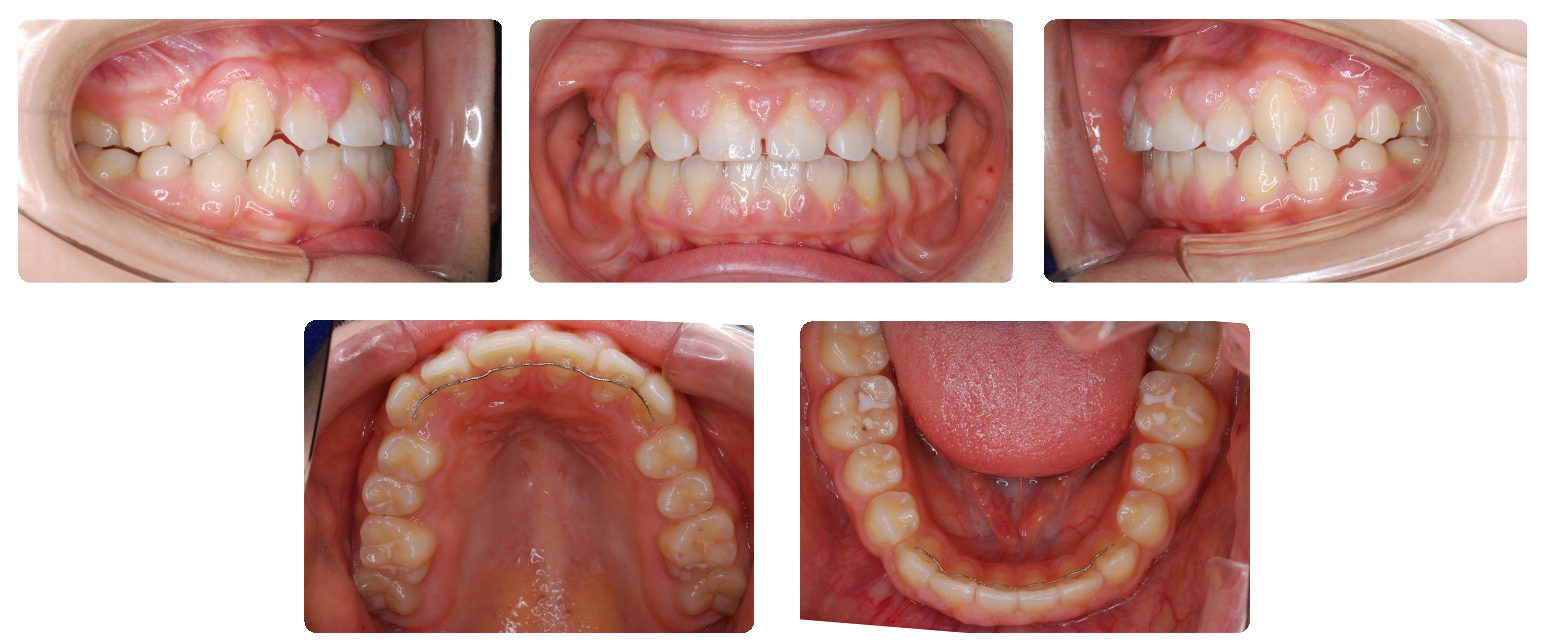

上あごの歯列幅を側方に拡大しながら左右犬歯の萠出スペースを少しずつ確保しました。永久歯がほぼ生え揃った時点で再診断を行い、非抜歯で治療を進めることになりました。

上下顎の歯列にマルチブラケット装置(ワイヤーによる本格矯正治療)を装着して永久歯の矯正治療を開始しました。

治療途中で服用薬の副作用による歯肉腫脹の状態を考慮して、動的処置の最終仕上げの前でところどころに至らない箇所がありますがいったん上下顎の装置を外して保定に移行しました。